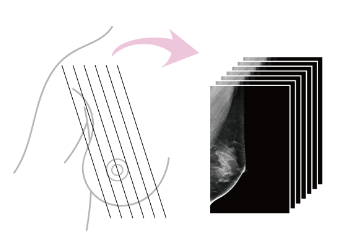

3Dマンモグラフィ(トモシンセシス)とは

- 通常の2Dマンモグラフィ同様に乳房を圧迫しながら挟んで撮影します。

- 撮影時間は5〜8秒ほどで通常の撮影より少し長めです。

- 撮影した画像はCTやMRIなどの断層撮影のように一度の撮影で複数枚の画像が得られます。

- 被ばくは通常のマンモグラフィ検査とほぼ同等です。